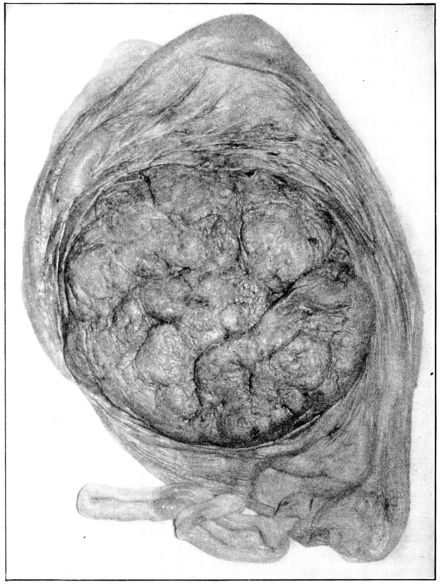

23. Maternal surface of the placenta 74

24. Fetal surface of the placenta 75